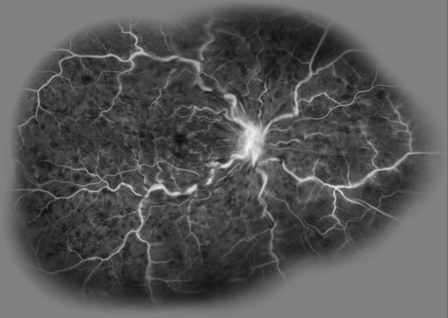

Fluorescein Angiography

In nonischemic CRVO, FA shows marked delay in arteriovenous transit time, which is longer than 20 seconds, masking by retinal hemorrhages, and vessel wall staining. Late staining along the large retinal veins is a characteristic finding in moderate and severe degrees of central retinal vein obstruction. The ischemic form has extensive areas of capillary nonperfusion. Greater than 10 disc areas of retinal capillary nonperfusion is associated with an increased risk of neovascularization.

A timed fluorescein angiographic study, preferably using a wide-angle fundus camera, can document the degree of obstruction, the severity of the capillary permeability alterations, and the extent of the retinal capillary nonperfusion especially after at least partial resolution of the intraretinal hemorrhages . It is important to include views of the peripheral fundus and the posterior pole, since capillary nonperfusion is most likely to occur in these areas. In the presence of widespread confluent hemorrhages, it may not be possible to determine angiographically the extent of capillary closure.